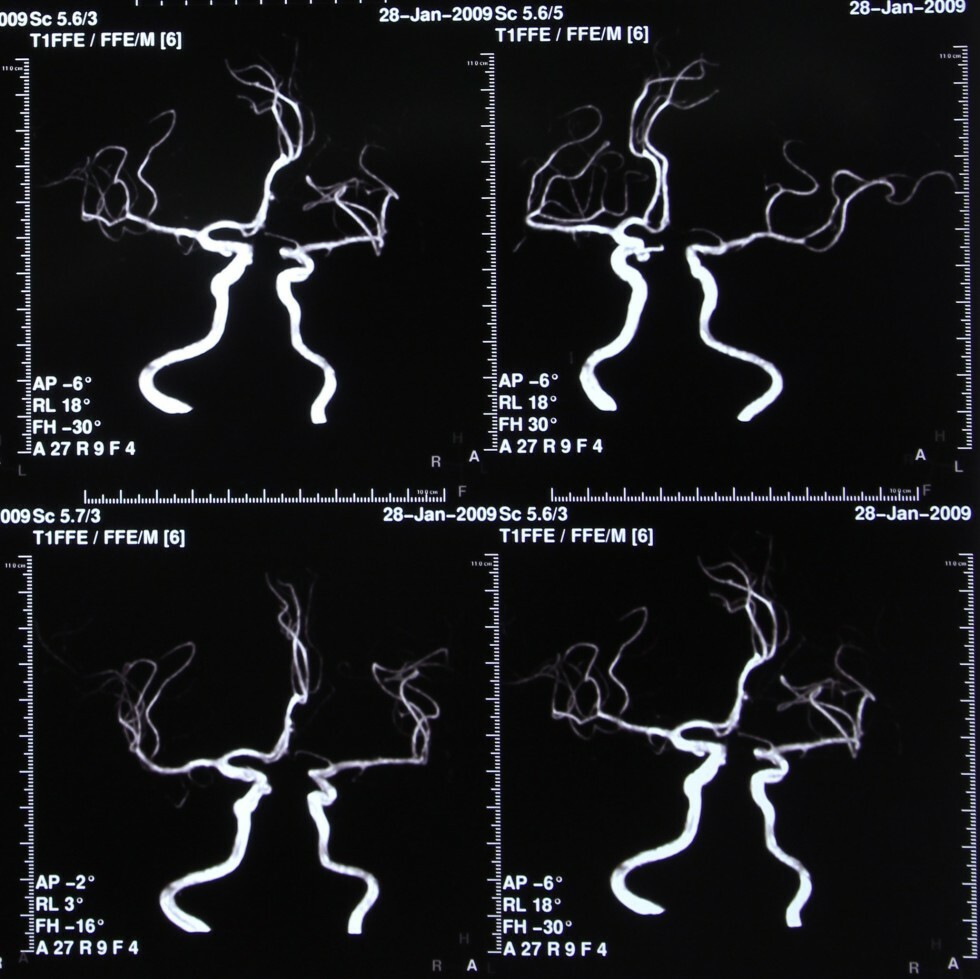

Intracranial MRA images collage

Intracranial MRA

MRA stands for magnetic resonance angiography. It is an MRI study of the blood vessels. MRAs are used to assess abnormalities in the blood vessels of patients with a history of stroke, aneurysm, heart disease, and atherosclerotic vascular disease.

Your doctor might recommend an MRA if you suffer from frequent headaches. Often, MRAs also are used to evaluate problems with blood vessels such as disease and narrowing or enlargement. Additionally, MRA is helpful in detecting disease in arteries supplying blood to the brain and the development of atherosclerosis, a condition that can lead to stroke. MRA is a useful tool to detect aneurysms and evaluate your veins.